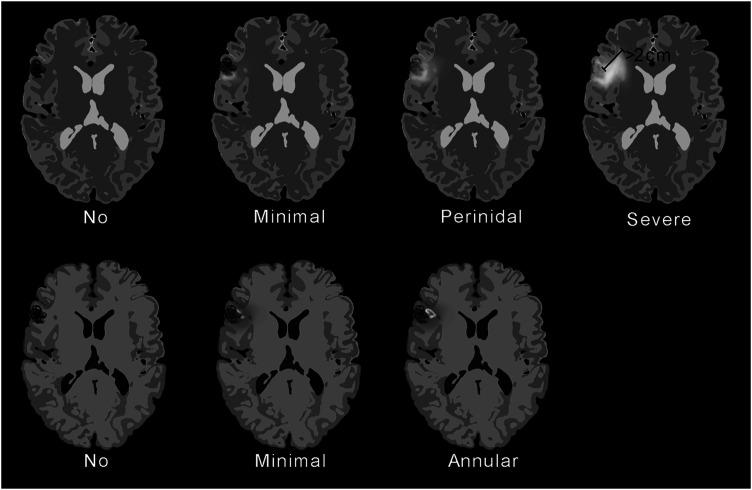

Retrospective review of pre- and post-treatment digital subtraction angiography and MRI and medical records in 30 patients with AVMs treated with proton radiation. Patients were treated with two or five fractions; total radiation dose was 20-35 physical Gy. Vasogenic edema (minimal, perinidal, or severe), contrast enhancement (minimal or annular), cavitation and nidus obliteration (total, partial, or none) were assessed.

26 of 30 patients (87%) developed MRI changes. Vasogenic edema was seen in 25 of 30 (83%), abnormal contrast enhancement in 18 of 26 (69%) and cavitation in 5 of 30 (17%). Time from treatment to appearance of MRI changes varied between 5 and 25 months (median 7, mean 10). Seven patients developed new or deteriorating symptoms that required treatment with corticosteroids; all these patients had extensive MRI changes (severe vasogenic edema and annular contrast enhancement). Not all patients with extensive MRI changes developed symptoms. We found no relation between MRI changes and nidus obliteration.